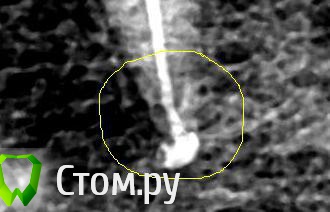

Л-Ф Опубликовано 23 апреля, 2014 Автор Поделиться Опубликовано 23 апреля, 2014 Вот я сделала Контраст снимка в программе и увидала,что плохо запломбировано внизу у корня....... Проверьте,кто-нибудь хорошенько.Боль острая.при смыкании зубов Ссылка на комментарий

Л-Ф Опубликовано 24 апреля, 2014 Автор Поделиться Опубликовано 24 апреля, 2014 Вот пожалуйста,сделала фото корня зуба с Контастом.Тут ясно видно плохое заполнение.Как вы считаете? Жду советы Ссылка на комментарий

red_butler Опубликовано 24 апреля, 2014 Поделиться Опубликовано 24 апреля, 2014 канал нормально запакован Ссылка на комментарий

Гарриевич Опубликовано 24 апреля, 2014 Поделиться Опубликовано 24 апреля, 2014 В пределах канала корня все плотно запломбировано Ссылка на комментарий